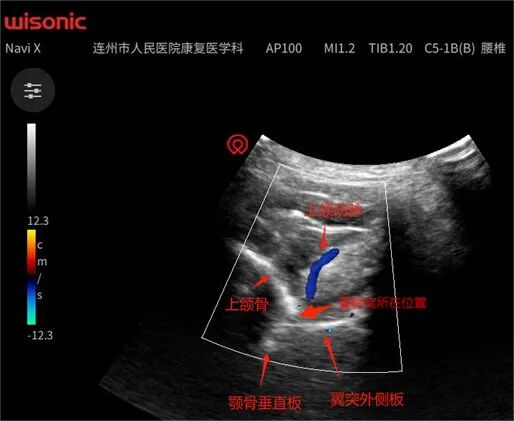

蝶腭神经节阻滞是按中西医结合的理论及方法,于20世纪60年代问世的一种治疗过敏性鼻炎的穴位疗法。目前通过大量的临床病例证实,干预蝶腭神经节(半月神经节)可以快速调节交感神经与副交感神经的动态平衡,从而发挥治疗过敏性鼻炎的作用。在2018年《中国过敏性鼻炎诊治指南(英文版)》中,已经明确推荐通过干预蝶腭神经节来治疗过敏性鼻炎。近年来,随着肌骨超声可视化技术的推广运用,弥补了传统盲视治疗的缺陷,在肌骨超声可视化的引导下,不仅可以清晰地显示翼腭窝,即蝶腭神经节所在的翼腭窝的位置,从而能精准针刺或注射,而且可以显示上颌动脉,有助于治疗过程中避开血管,减少治疗的并发症。